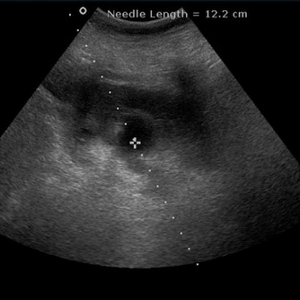

Aby lepiej zrozumieć, o co w tym chodzi, oto kilka zdjęć ze szpitali specjalistycznych: